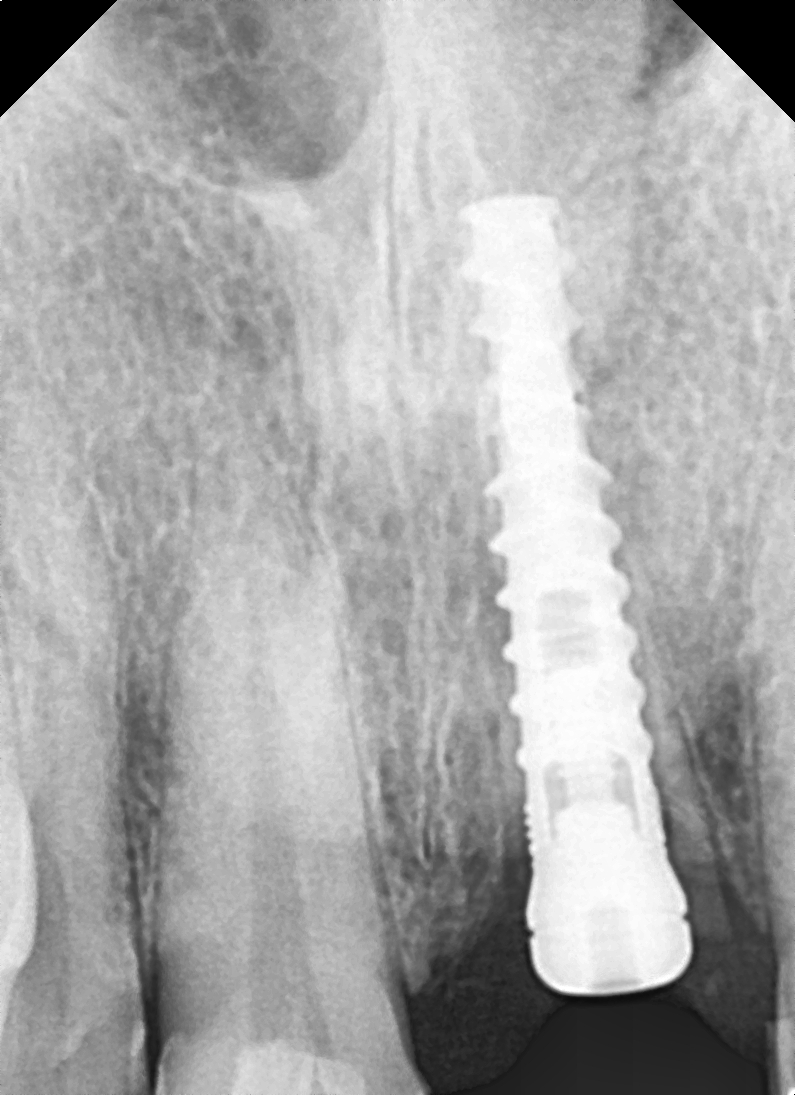

Images Of Dental Treatment Servcies Done At Our Hospital